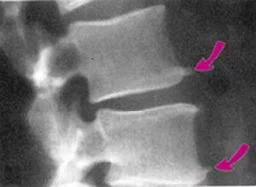

增生的骨赘通常在骨骼的两端四周同时存在,但投影在平面的X线片上,可能仅表现为基底宽、尖端细的粗刺形状。